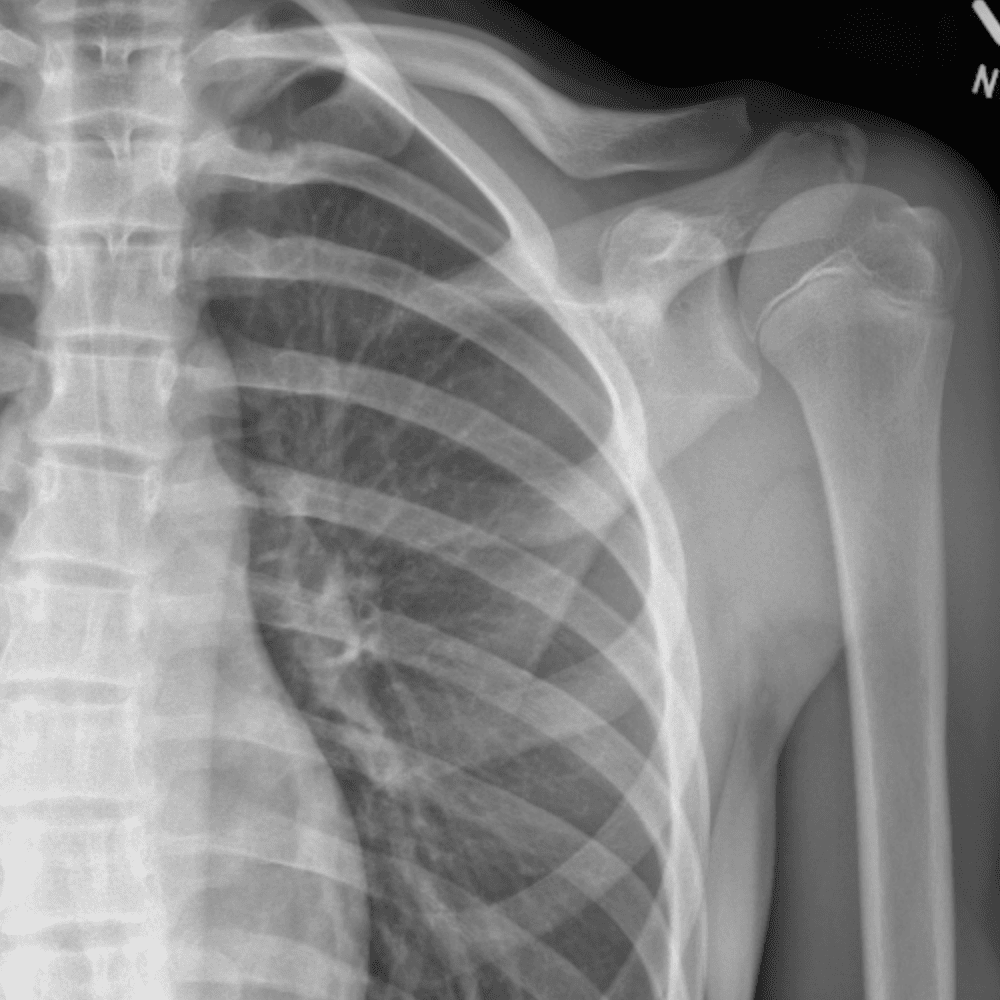

Simuliert den Dienst durch subtile oder schwierige Fälle und einige Normalbefunde.

30 Fälle